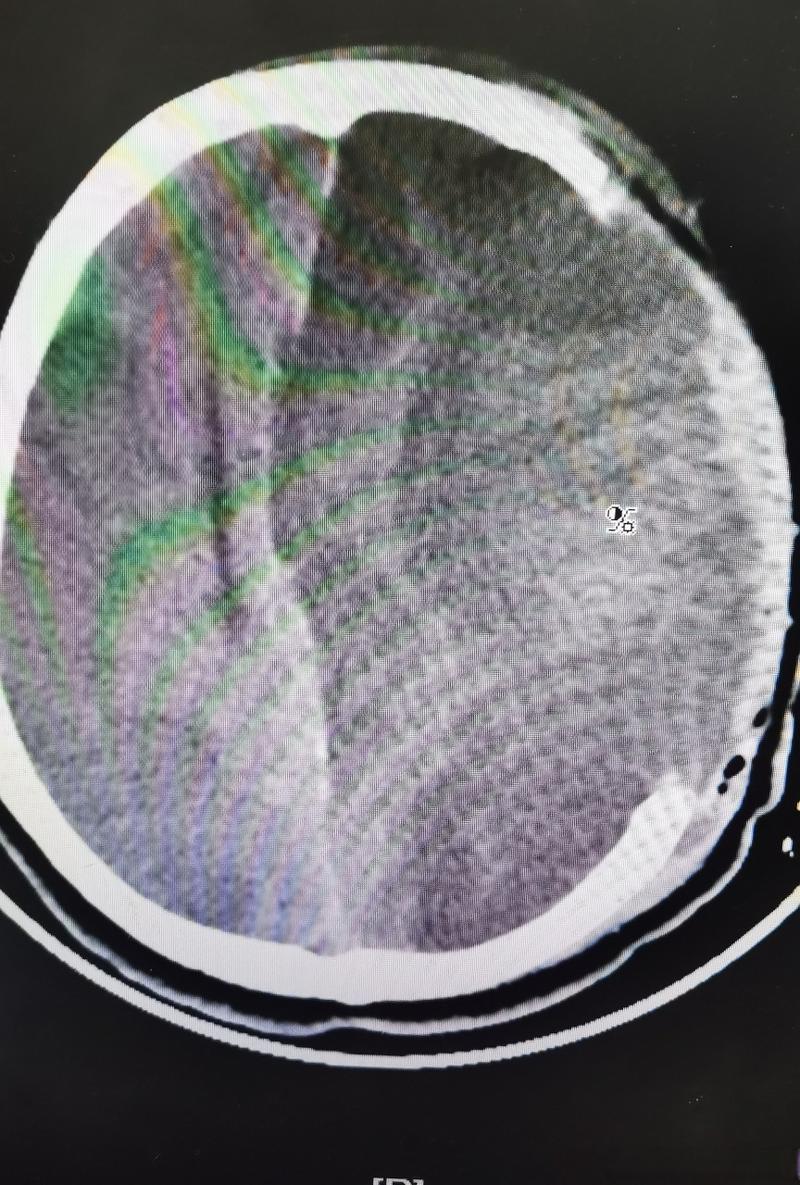

“脑梗后脑水肿轻度脑疝”描述的是一个恶性循环,情况正在急剧恶化,每分每秒都至关重要。

- 脑梗(Stroke / 脑血管堵塞): 大脑的某根血管堵塞了,导致该血管供应的脑细胞因为缺血缺氧而死亡,就像一块田地因为水管堵了而干枯。

- 脑水肿(Brain Edema): 脑细胞死亡后,会引发周围健康脑组织的炎症反应和液体渗出,导致大脑像海绵吸水一样肿胀起来,肿胀的大脑体积会增大。

- 脑疝(Brain Herniation): 我们的大脑被坚硬的颅骨包裹着,空间是固定的,当脑水肿导致大脑体积急剧增大,颅骨内的压力就会急剧升高(颅内压增高),增高的压力会把大脑的一部分组织从一个结构挤到另一个结构中,这个过程就叫“脑疝”。

- “轻度脑疝”:这是一个非常危险的信号,说明脑疝已经发生,但可能还处于早期阶段。“轻度”绝不意味着“不严重”或“可以观察”,它是一个警告,预示着如果不立即干预,病情会迅速恶化成“重度脑疝”,导致呼吸心跳停止,危及生命。